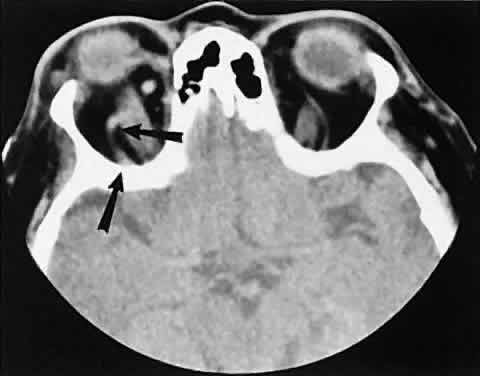

Radiographic evaluation can show either infiltrative or circumscribed masses. Some tumors display a predilection for metastasizing to certain structures, such as prostate carcinoma to bone and cutaneous melanoma to EOMs (Fig. 21). Evidence of bilateral disease at presentation ranges from 7% to 9%, with the prime example being neuroblastoma.71

Fig. 21. A. Axial view shows bilateral involvement from metastatic breast carcinoma. An amorphous infiltrative soft-tissue mass is more apparent in the right orbit, which encases the globe, producing clinical and radiographic enophthalmos. Cutaneous melanoma metastatic to the superior rectus muscle is depicted on axial (B) and coronal (C) views. A locally enhancing and asymmetric enlargement is restricted to the right superior rectus muscle. These features distinguish this lesion from Graves' orbitopathy.